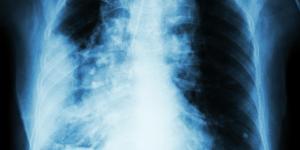

cancer des poumons

Radiothérapie pulmonaire guidée par GPS